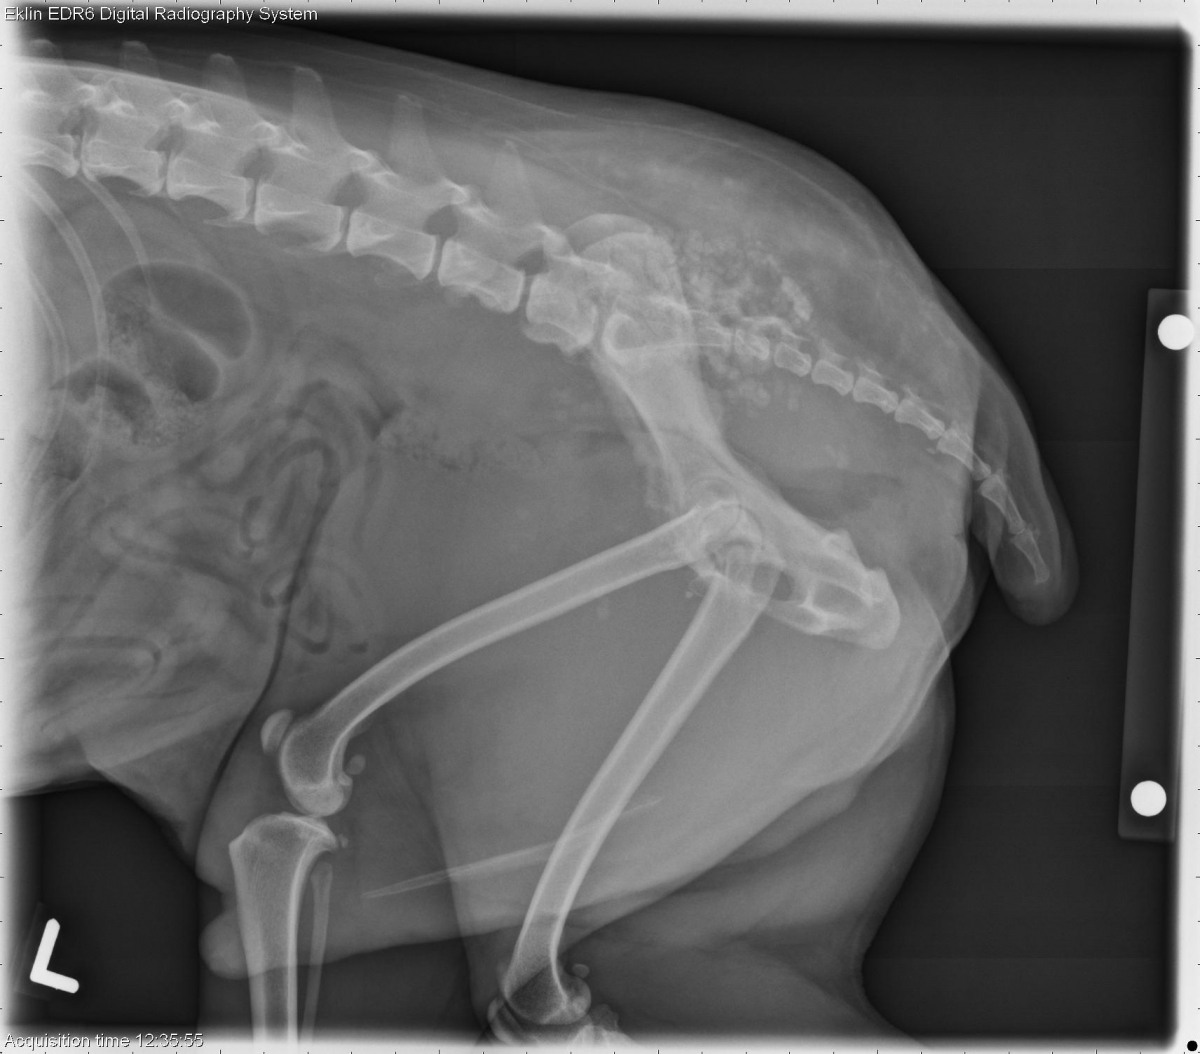

10 year old male neutered Rat Terrier with difficulty defecating and left pelvic limb lameness and swelling. What are your findings?

L LAT Pelvis

Pelvis: There is increased soft tissue opacity in the region of the prostate gland with multifocal mineralization. The colon is deviated dorsally, and there is sclerosis and periosteal reaction on the L7 vertebra. There is irregular new bone production arising from the left ilium with an associated soft tissue mass. There is ventral deviation of the rectum caudal to the ilium on the lateral projection secondary to the mass.

Prostatic carcinoma with metastasis to the spine, pelvis, and lungs